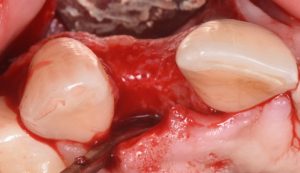

This video demonstrates implant placement in the esthetic zone combined with simultaneous guided bone regeneration (GBR). The case focuses on surgical decision-making, specifically how to determine when a staged approach is indicated versus when simultaneous implant placement and GBR can be predictably performed.

The procedure is presented step by step, including flap design and management, defect assessment, membrane selection and stabilization, flap advancement, and suturing techniques. Emphasis is placed on achieving tension-free closure and maintaining hard and soft tissue contours critical for esthetic success.